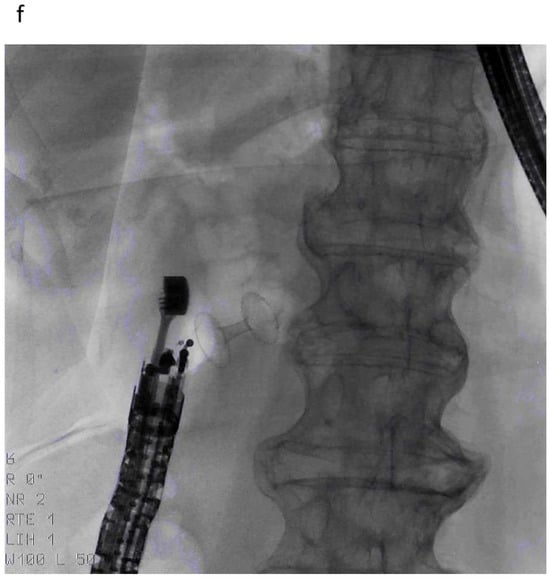

10. Plastic or Metal Stents?

3. Why Do We Need Procedures Other Than ERCP?

6.1. Arguments in Favor of PTBD

6.2. Arguments Against